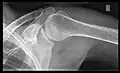

Shoulders

These include:

- AP-projection 40° posterior oblique after Grashey

The body has to be rotated about 30 to 45 degrees towards the shoulder to be imaged, and the standing or sitting patient lets the arm hang. This method reveals the joint gap and the vertical alignment towards the socket.[17]

- Transaxillary projection

The arm should be abducted 80 to 100 degrees. This method reveals:[17]

- The horizontal alignment of the humerus head in respect to the socket, and the lateral clavicle in respect to the acromion.

- Lesions of the anterior and posterior socket border or of the tuberculum minus.

- The eventual non-closure of the acromial apophysis.

- The coraco-humeral interval

- Y-projection

The lateral contour of the shoulder should be positioned in front of the film in a way that the longitudinal axis of the scapula continues parallel to the path of the rays. This method reveals:[17]

- The horizontal centralization of the humerus head and socket.

- The osseous margins of the coraco-acromial arch and hence the supraspinatus outlet canal.

- The shape of the acromion

This projection has a low tolerance for errors and accordingly needs proper execution.[17] The Y-projection can be traced back to Wijnblath's 1933 published cavitas-en-face projection.[18]

In the UK, the standard projections of the shoulder are AP and Lateral Scapula or Axillary Projection.[15]